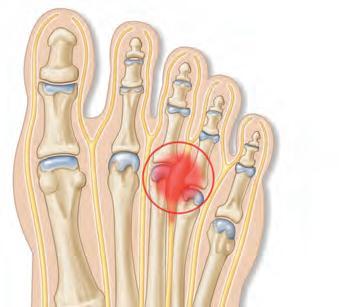

олезнь: артрит суставов Какие органы поражает: суставы, связки и кости Причины: инфекции, нарушение обмена веществ, повышенная кровоточивость из-за кровоизлияний в сустав, аутоиммунное воспаление Симптомы: боль, припухлость, покраснение кожи над пораженным суставом, ограничение подвижности, повышение температуры тела, усталость и/или слабость, нарушение аппетита Осложнения: повреждение и деформация суставов, туннельный синдром, повреждение спинного мозга Врач: терапевт, ревматолог Лечение: медикаментозное, местное, физиотерапия, массаж, гимнастика, артродез, в некоторых случаях - хирургическая замена сустава Профилактика: снижение веса, занятия спортом

– это собирательное

распространены такие виды патологии: ревматоидный, подагрический, септический, реактивный и идиопатический. Артрит и артроз – взаимосвязанные явления, но не одно и то же. Артрит – воспаление сустава, артроз –разрушение, износ сустава. Эти явления почти всегда сопровождают друг друга, но знак равенства между ними ставить нельзя.

кислоты в суставах. Они провоцируют сильную боль, отек и покраснение вокруг сустава. Подагру ещё называют «болезнью аристократов». Это связано с тем, что обострение подагры вызывает потребление в больших количествах красного мяса, морепро-